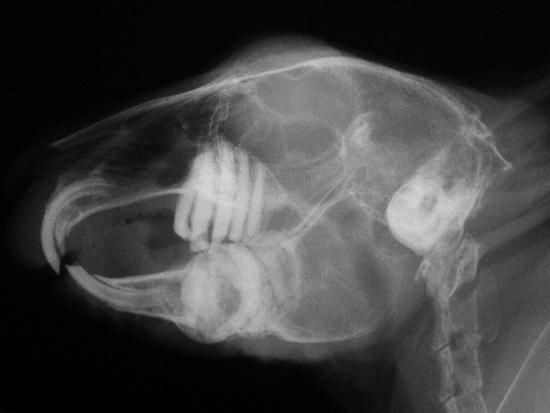

Варто зазначити, що для підтвердження діагнозу необхідно зробити рентген. На зображенні нижче наведено приклад нормального стану коренів зубів кролика.

А тут видно, що коренева система розрослася.

Проблеми з щелепою у кроликів